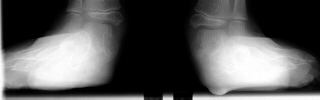

A six year old female followed for spastic quadriplegic cerebral palsy presented with increasing difficulty with ambulation secondary to bilateral hamstring tightness and progressive planovalgus deformity of the feet. Examination revealed a small thin six year-old female with severe bilateral planovalgus deformity which has become a progressive problem. While walking, the bilateral planovalgus deformity causes her to bear weight on her medial midfoot.

On weight bearing x-rays the talocalcaneal angle is 44 degrees and talonavicular angle is 40 degrees. This indicates that surgery is definitely indicated.